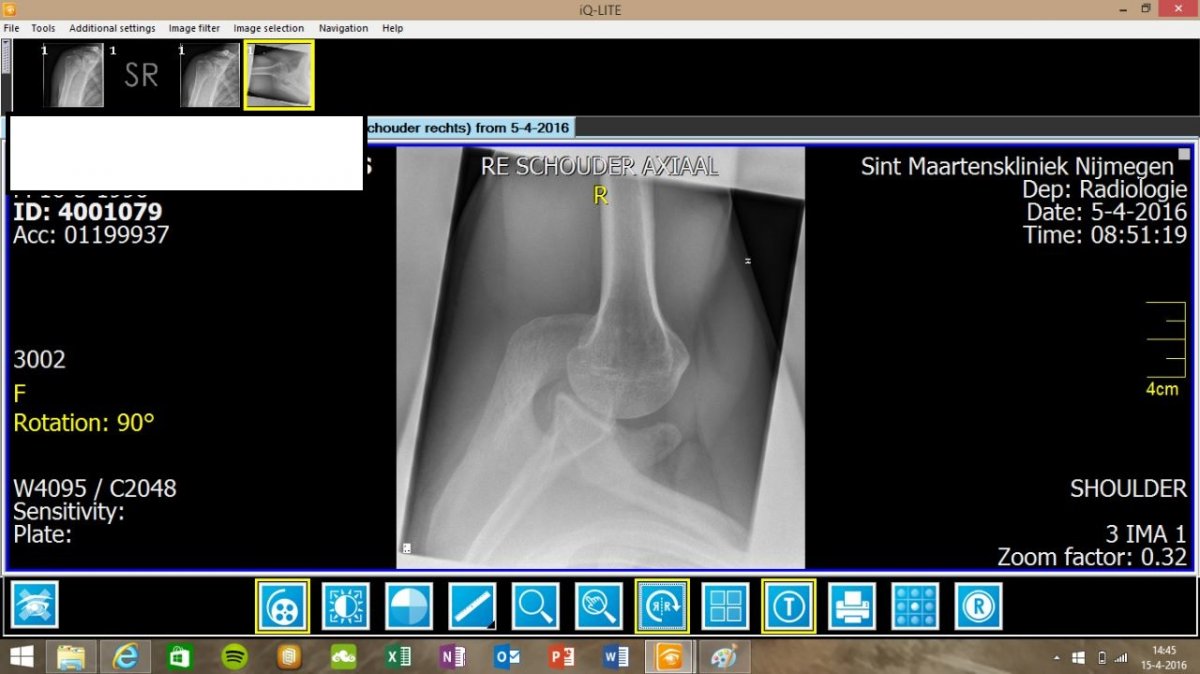

Vandaag bij viasana geweest voor de uitslag van de mri, bicep was geïrriteerd en vocht in de slijmbeurs maar voor de rest zag de schouder er goed uit volgens de orthopeed.

Dit is natuurlijk logisch aangezien ik al dik 3 maanden thuis zit en mijn schouder rust heeft. Ook wilde de orthopeed niet toegeven dat er teveel van het acromion is afgehaald, ondanks de second opinion arts dit wel concludeerde. Hij kon niks meer voor me doen alleen doorverwijzen naar een manueel, dit heeft geen nut aangezien ik hier al een dik jaar loop zonder verbetering. Vorige week voor het eerst sinds lange tijd gewerkt en veel pijn gehad in de achterkant van mijn schouder, zelfs in rust is de achterzijde volledige over de zeik, veel pijn. Ik heb ook nog nooit pijn gehad in de achterzijde van mijn schouder voor de ingreep, nu is het een groot drama. De pijn is niet te harden zelfs in rust.

Zie bijlage voor echo schouder na de ingreep.